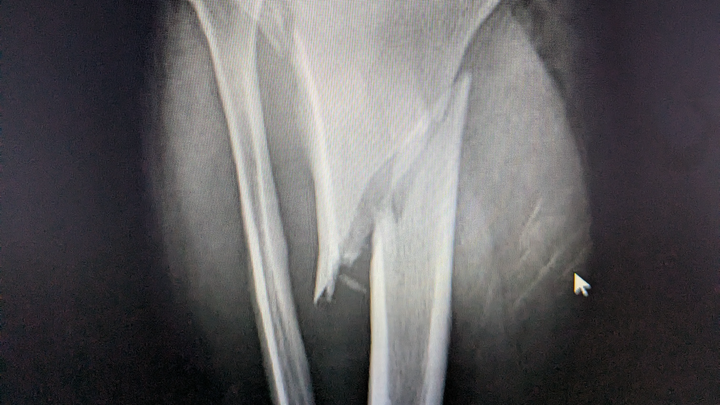

I wanted to share an update on our journey. While Adam is mostly healed physically, we are still struggling deeply with the financial and emotional aftermath of the accident.

As many of you know, he was hit in April while selflessly stopping to move large pieces of tire debris off the highway to keep other drivers safe. It is heartbreaking that since then, the person who hit him has chosen to sue us for damage to her car. Not to mention that we can't sue her and, even though he was at work, this injury was not covered by worker's comp because moving debris out of the road is " not part of his job". Because of that, we have had to pay for everything. We are grateful that the court immediately dismissed the ticket he received for being on the roadway, recognizing he was only trying to help. This has been an incredibly taxing year, and we are so thankful for any support you can provide.